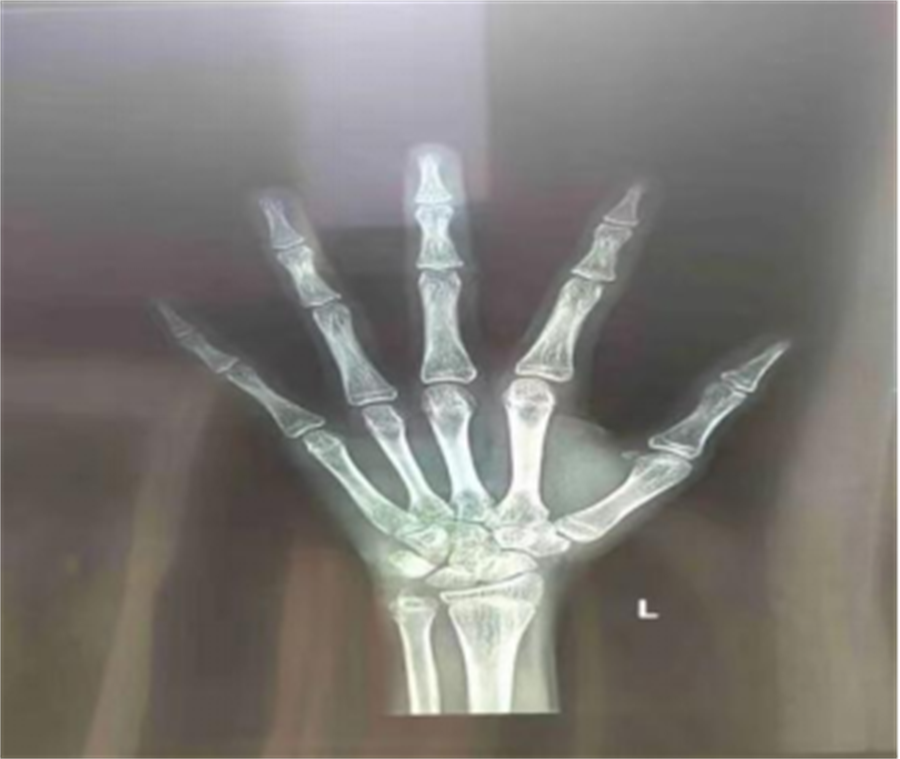

什么是骨龄?

骨龄:骨龄全称骨骼的年龄,它是以小儿骨骼实际发育程度同标准发育程度进行比较,所求得的一个发育年龄。骨龄在很大程度上代表了儿童真正发育水平。

人类骨骼发育的变化基本相似,每一根骨头的发育过程都具有连续性和阶段性。不同阶段的骨头具有不同的形态特点,骨龄评估能较准确地反映个体的生长发育水平和成熟程度。